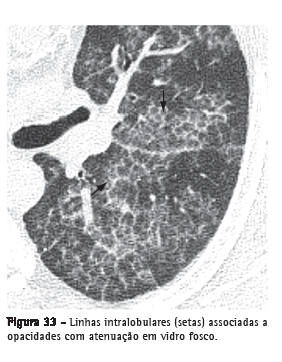

Linhas intralobularesCaracterizadas na TCAR como imagens lineares finas no interior do lóbulo pulmonar secundário e, quando acentuadas, resultam em um aspecto rendilhado fino (Figura 33). Este achado pode ser encontrado em diversas situações, destacando-se as doenças fibrosantes (por ex.: pneumonia intersticial usual) e aquelas associadas ao padrão de pavimentação em mosaico (por ex.: proteinose alveolar).(3,54)

Ver também Padrão reticular e Padrão de pavimentação em mosaico.